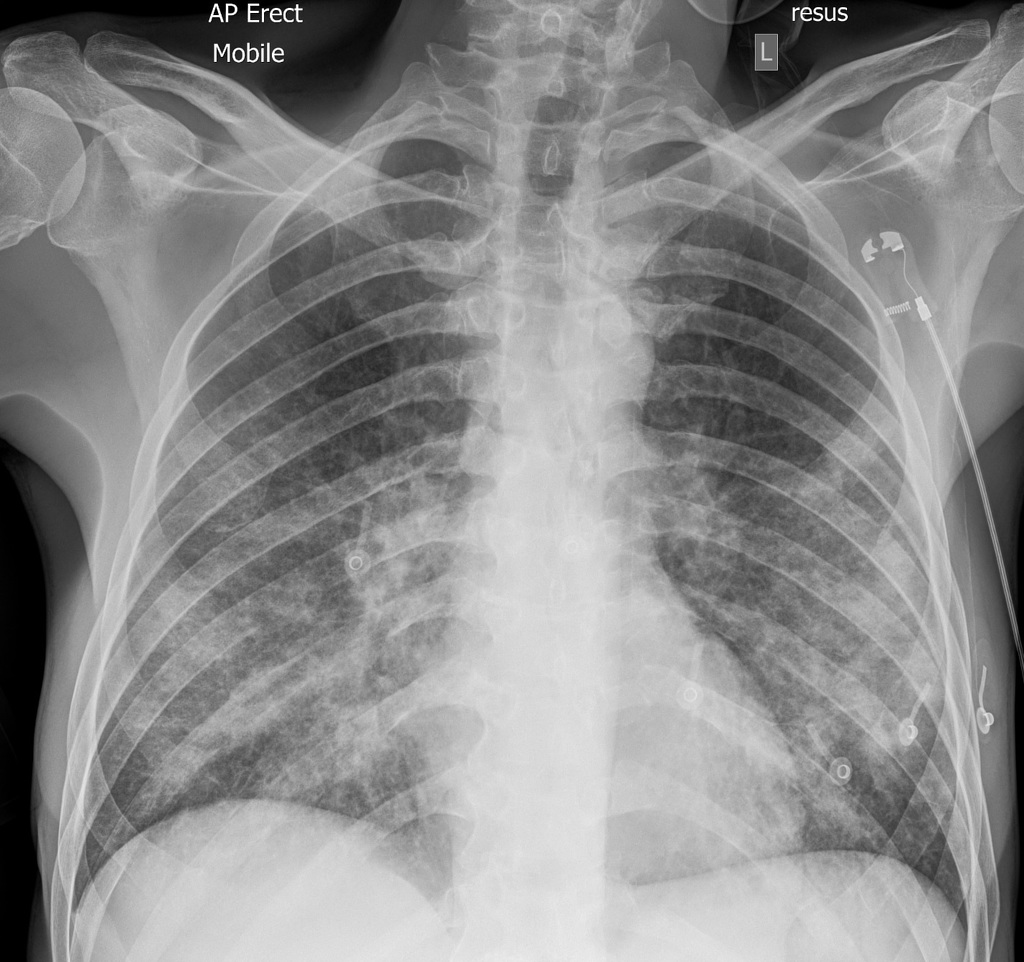

Example 2

Diagnosis

ECG